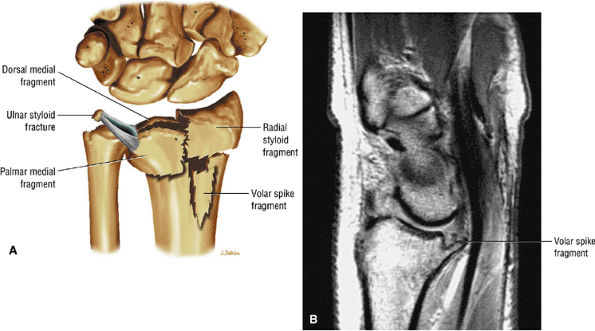

At the site of the radiolunate articulation, the distal articular surfaces of the radius and ulna are usually at the same level (i.e., neutral ulnar variance). Alternatively, the ulna may be relatively long (positive ulnar variance), leading to an ulnar abutment syndrome, or relatively short (negative ulnar variance), as is often seen in Kienböck's disease. The distal radius forms two facets that articulate with the scaphoid and lunate of the proximal carpal row. This articulation of the proximal pole of the scaphoid in the scaphoid fossa is quite congruent, and even a small degree of malrotation of the scaphoid may cause incongruent loading of the articular cartilage and subsequent degeneration (such as that which accompanies a SLAC wrist, as described by Watson and Ryu37). The lunate facet commonly becomes incongruent following distal radius fractures, especially die-punch-type fractures. The interosseous ligaments join the proximal carpal bones at their proximal edges.36